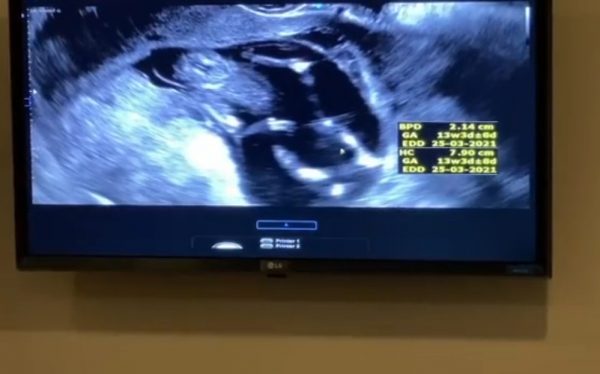

ล่าสุดนางเอกสาว ได้โพสต์คลิปวิดีโอ ภาพอัลตร้าซาวด์ลูกน้อย ในอินสตาแกรมส่วนตัวซึ่งมีผู้ติดตามจำนวน 3,260,727 คน พร้อมเผยความในใจว่า “ตื่นยัง ขาย้าวยาว กำลังหลับเลย ลูกหลับสนิทเลยค่ะ วันนี้ก็ 13 week แล้ว ลูกโตแล้ว แข็งแรงมาก แม่อยากเห็นหน้าลูกมาก ไม่ไหวแล้วค่ะ ตื่นเต้นที่สุดเลย”